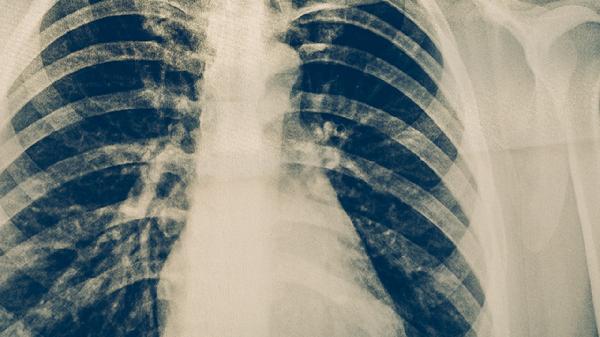

肺癌中晚期症状主要有咳嗽、痰中带血或咯血、胸痛、气促、声音嘶哑等。肺癌中晚期通常指肿瘤局部进展或发生远处转移的阶段。

咳嗽是肺癌中晚期常见症状,多表现为持续性干咳或伴有少量白色泡沫痰。肿瘤侵犯支气管黏膜或引起阻塞性肺炎时可导致咳嗽加重。咳嗽可能与肿瘤刺激气道神经、继发感染等因素有关。患者应注意休息,保持室内空气湿润,避免吸入刺激性气体。

痰中带血或咯血多因肿瘤组织血供丰富、质地脆弱,咳嗽时血管破裂所致。咯血量可从痰中带血丝到大量咯血,严重时可导致窒息。此症状可能与肿瘤侵犯肺部血管、合并感染等因素有关。患者需保持镇静,采取患侧卧位,避免剧烈活动,并及时就医。

胸痛常表现为持续性钝痛或隐痛,位置固定。肿瘤侵犯胸膜、胸壁或肋骨时可引起胸痛,咳嗽或深呼吸时加重。胸痛可能与肿瘤直接侵犯、胸膜转移、肋骨转移等因素有关。患者可尝试调整体位缓解不适,但需明确病因后进行针对性治疗。

气促表现为活动后呼吸困难或静息时气短。肿瘤阻塞大气道、大量胸腔积液或淋巴管转移导致气体交换障碍时可引起气促。气促可能与气道阻塞、胸腔积液、肺不张等因素有关。患者应减少活动量,采取半卧位,必要时接受氧疗或胸腔穿刺引流。